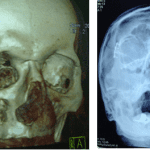

Η ιδιαιτερότητα των οστών του κρανίου και κυρίως του σπλαχνικού ως υμενογενή, προσδίδουν την ανάγκη για άμεση και γρήγορη όσο το δυνατόν αντιμετώπιση, λόγω της συντομότερης πόρωσής τους από τα άλλα οστά του ανθρώπινου σκελετού. Η καθυστέρηση χρονικά στην αντιμετώπιση των καταγμάτων του σπλαχνικού κρανίου, θα οδηγήσει πιθανόν σε φλεγμονές με αποστήματα, κακή πόρωση, ψευδάρθρωση, αδυναμία μάσησης και οδοντικής σύγκλισης, ασυμμετρία και παραμόρφωση του προσώπου, υπαισθησίες ή παραισθησίες νεύρων του προσώπου, κακή ανάταξη των καταγμάτων με πιθανή υποτροπή τους.

Επίσης Τα τελευταία χρόνια, αυξημένος παρουσιάζεται ο αριθμός των αυτόματων καταγμάτων σε ασθενείς που λαμβάνουν φάρμακα (διφοσφωνικά) για την οστεοπόρωση ή την οστεοπενία, αλλά και σε ασθενείς που λαμβάνουν θεραπείες για νεοπλάσματα (πχ χημειοθεραπείες). Γίνεται λοιπόν κατανοητό, πόσο σημαντική είναι η όσο το δυνατόν γρηγορότερη χρονικά παρέμβαση με ανάταξη των οστών του σπλαχνικού κρανίου σε περίπτωση καταγμάτων του.

Οι τεχνικές οστεοσύνθεσης με μικρού μεγέθους πλάκες είναι σήμερα οι πλέον συνήθης. Μεταλικές ή και απορροφήσιμες πλάκες τοποθετούνται ανάλογα με την περίπτωση του κατάγματος. Πολλές φορές χρειάζεται και δεύτερη παρέμβαση, λόγω καθυστερημένης χρονικά ανάταξης του κατάγματος, για τη διόρθωση της όχι καλής πόρωσης ή σύγκλισης του τραύματος, με χρήση διαφόρων ιστών όπως οστικό μόσχευμα από το κρανίο ή το ανώνυμο οστό. Με το πλεονέκτημα της καλής γνώσης των οστών του κρανίου το αποτέλεσμα είναι στην πλειονότητα το ευνοϊκότερο.